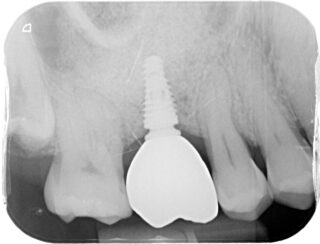

Once healing is complete, a custom-made dental crown is fitted onto the implant. This restores both the function and natural look of the missing tooth.